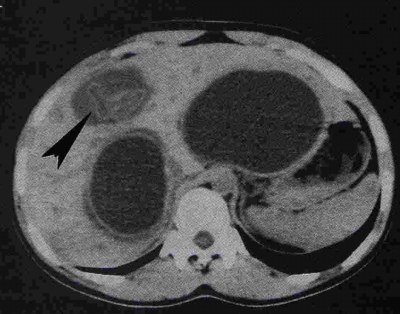

- בטומוגרפיה ממוחשבת ניתן לראות גוש בכבד (תצלום 25.10).

| תצלום 25.10: ציסטות מרובות בכבד. מימין הציסטות הן חלק ממחלה פוליציסטית מערכתית. משמאל ציסטות המוגבלות לכבד בלבד. | |